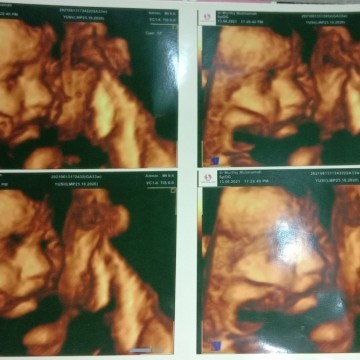

biasanya karna udah sempit bund ruang geraknya.. nih wajah baby ku nampak jelas pas usia kandungan 33week.

itu kliatan bun.. mata-hidung-mulutnya, kalo kata dokter usia pas kalo USG full itu diatas 20minggu & sblm 28 minggu

biasanya untuk usia 25-30an itu bagus buad liat muka janin.. tp tergantung jg posisi janinnya bun